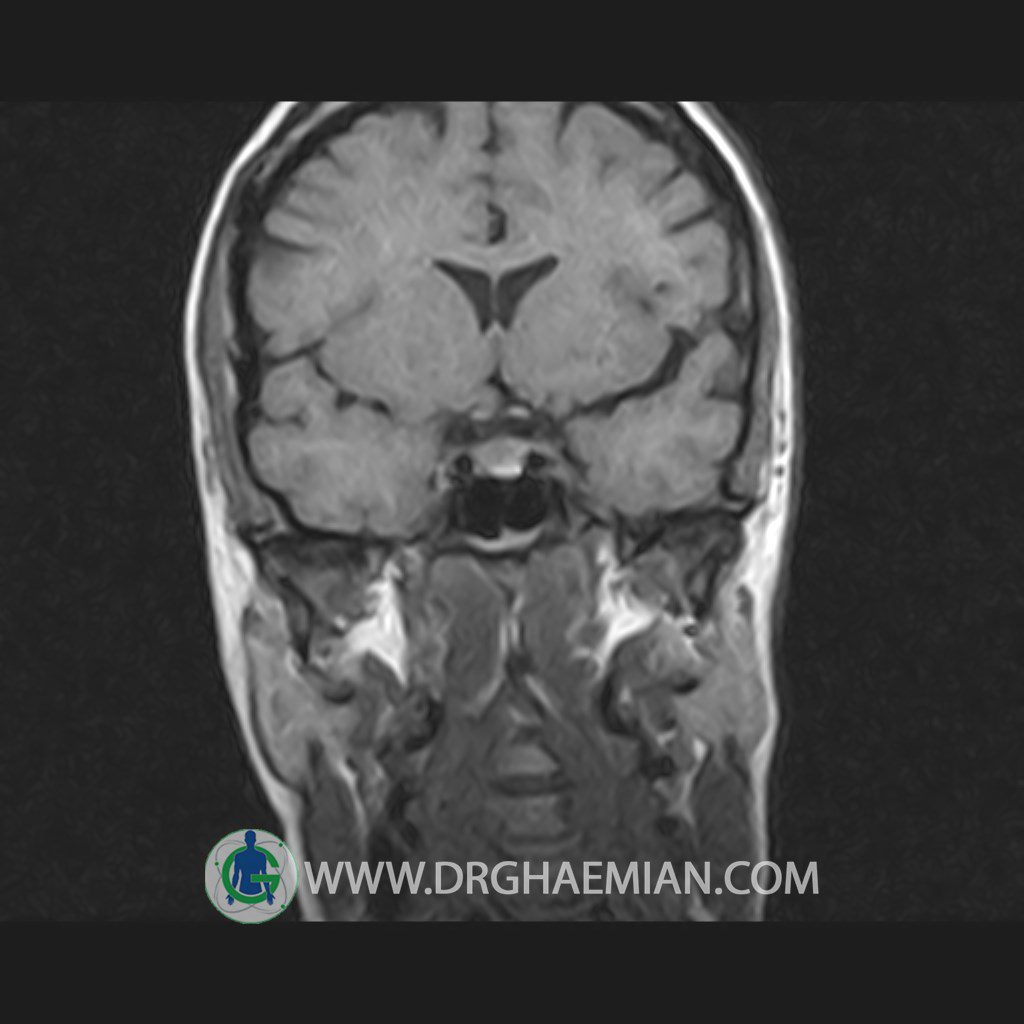

پزشکان اغلب از تصویربرداری ام آر آی برای تشخیص و درمان عارضه های پزشکی که فقط با استفاده از اشعه ایکس یا میدان مغناطیسی و امواج رادیویی قابل مشاهده است، استفاده می کنند. دستگاه ام آر آی تصاویر دقیق از ساختار های داخلی بدن ایجاد می کند. در این کیس هیپرپلازی هیپوفیز و آدنوم مشاهده می شود.

HYPOPHYSIS MRI

(with and without contrast)

Technique: Axial , coronal T1 , Axial , coronal , sagittal T2 , Axial, coronal T1 post Gd & 64 dynamic thin coronal slices.

The sella shows normal size , position and configuration .

The borders of its floor and walls are smooth and sharply defined .

The infundibulum is centered and of normal size .

The optic chiasm and suprasellar spaces appear normal .

The cavernous sinus and imaged portions of the internal carotid artery and carotid siphon are unremarkable .

Evaluable portions of the neurocranium show no abnormalities .

The sphenoid sinus is clear and pneumatized .

– Mild convexity at superior border of pituitary gland with post contrast homogeneous enhancement suggestive for pituitary hyperplasia & iso signal adenoma

is seen